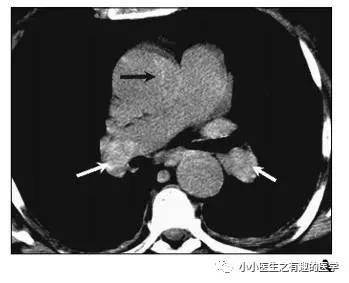

作者单位:Department of Radiology, Thoracic Imaging Section, San Francisco General Hospital。旧金山总医院。

如图,高密度影的那一条。不怕,有增强CT证实。

是不是很有趣。

再来一个图。

仔细看,有端倪。增强CT可以核实。

很明显,病人做了CT平扫,我们要仔细阅片,发现可疑,及时增强CT,要不然就漏诊了。